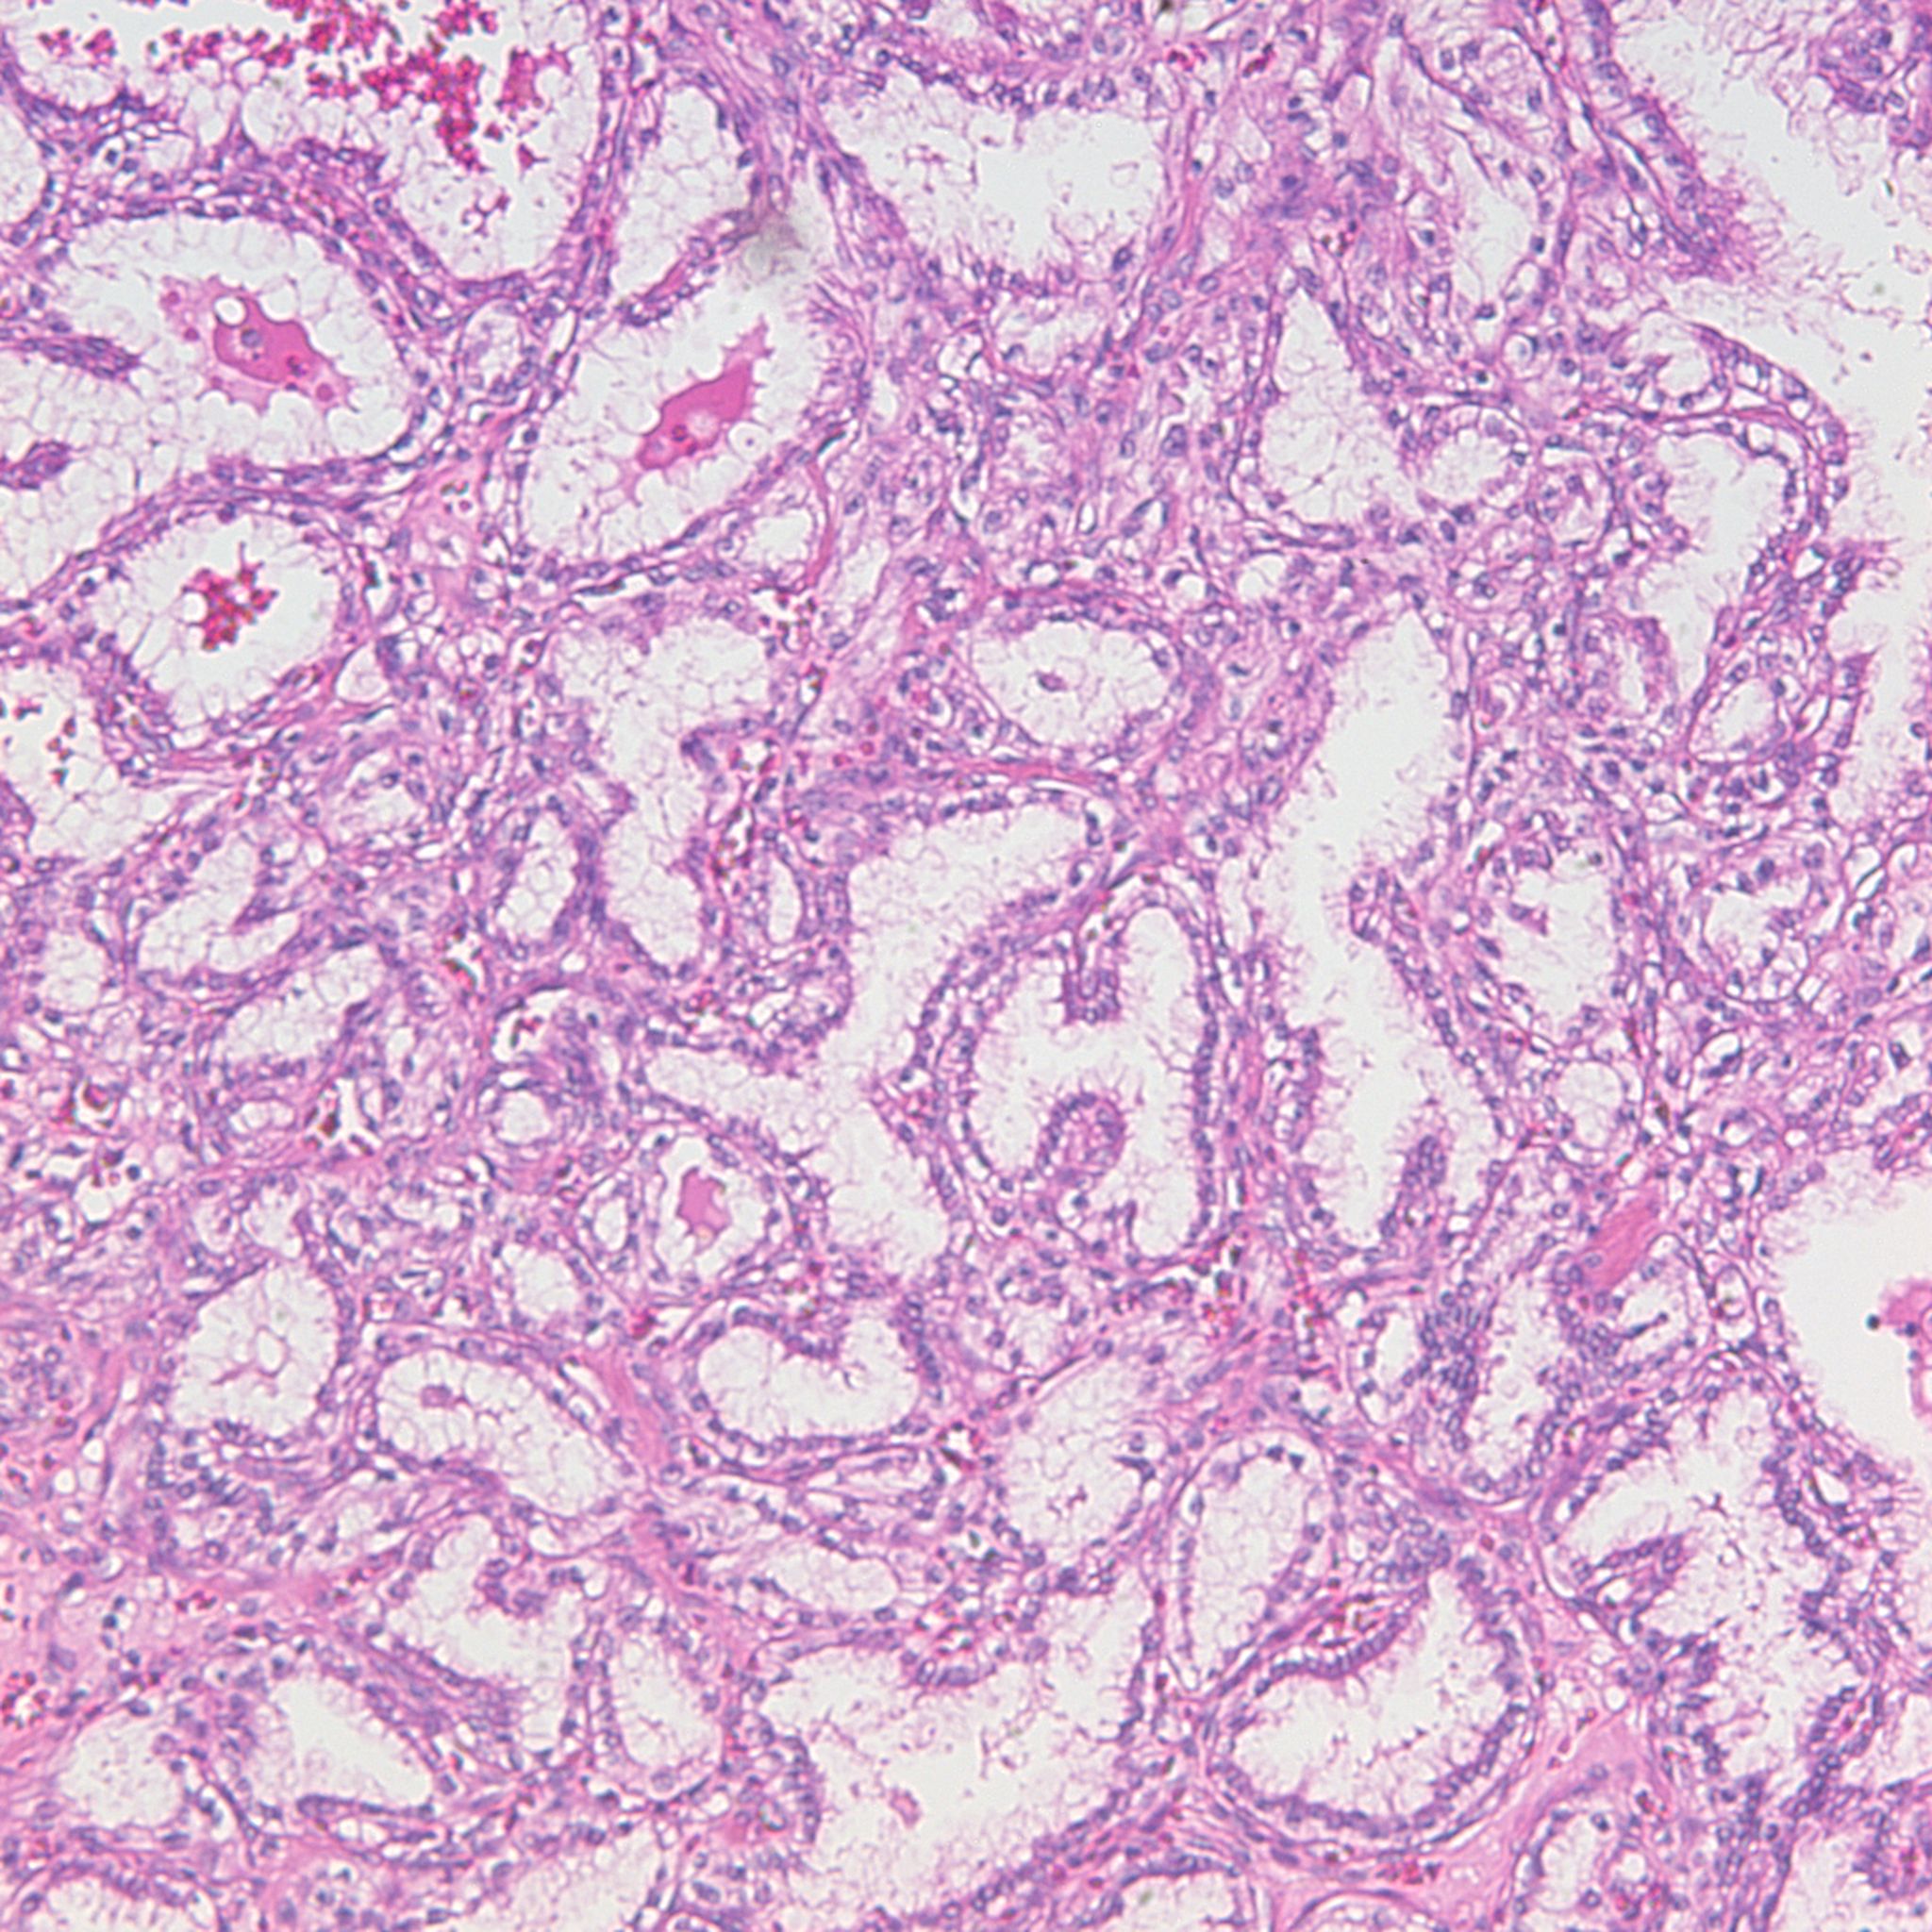

Classification of renal tumors

Case ID: 1220